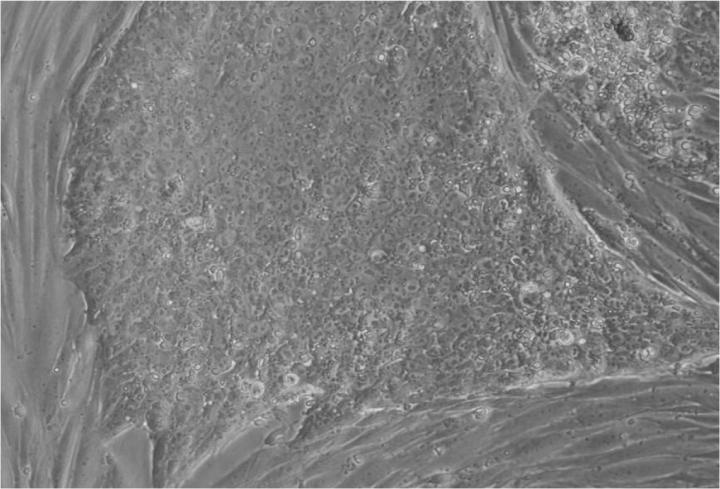

人類胚胎干細胞 (ESC) 是從囊胚(一種非常早期的人類胚胎)中發現的少量細胞產生的。從囊胚中取出的單個細胞生長成大量細胞以產生 ESC“系”。

胚胎干細胞研究的重點是干細胞系。這些是細胞群,都攜帶相同的基因,在實驗室中通過許多代細胞的許多生長和分裂周期生長。一個細胞系可以為許多研究人員提供大量細胞。

Jenny Nichols 拍攝的人類囊胚和人類胚胎干細胞圖像。愛丁堡大學 MRC 再生醫學中心向 SCNT 和多莉羊注射細胞核。